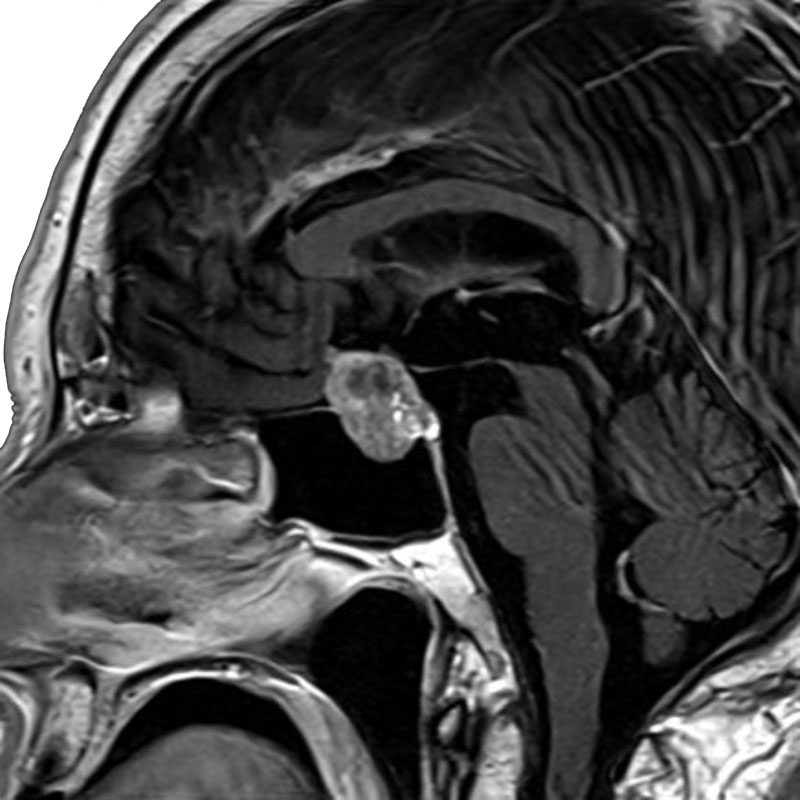

脳動静脈奇形

血管塞栓術

松田/濵田/元永